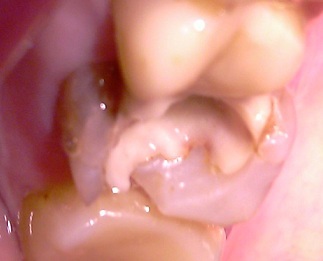

На этом снимке виден начальный процесс отслоения пломбы.

Если не решить проблему вовремя, то ситуация заметно ухудшается.

Здесь очевидно, как глубоко отслаивается пломба. Причина этой проблемы - ошибочный путь восстановления зуба.